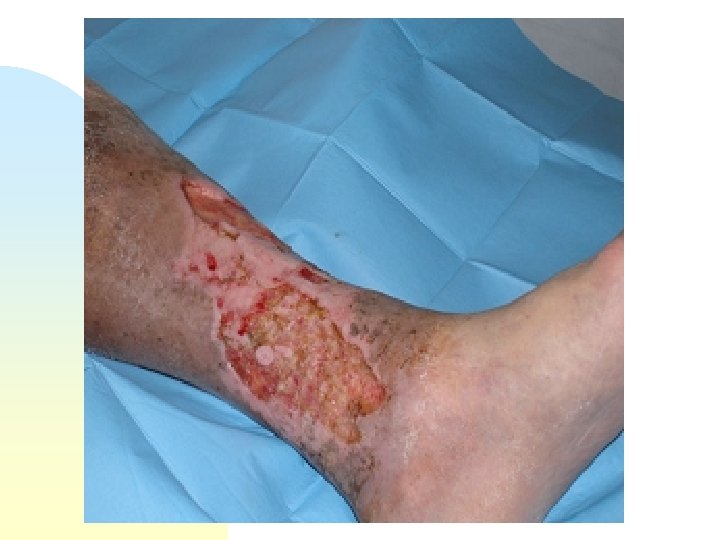

Donna (Z. A. ) di anni 80 con ulcera alla gamba di sinistra delle dimensioni di cm 11 x 8 formatasi da circa 2 anni; operata di by pass. Vascolarizzazione sufficiente.